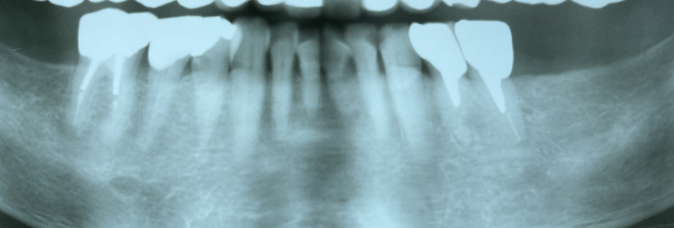

上あごの奥歯のむし歯に継発して歯根が感染を起こすと、鼻汁や鼻漏さえ伴う歯性上顎洞炎を生じることがあります。これも鼻が悪いからと放置して慢性化している人が多いように感じます。従来の歯科用エックス線撮影で左右の上顎洞の影の違いから見つかることもありますが、歯科用CT撮影ではより明確に上顎洞の状況を観察することができます。歯科での治療が中心になりますが、耳鼻科医との連携が必要になることもあります。

従来のX線撮影では、赤い矢印側で歯の上方が反対側に比べてやや白く見えるが明瞭ではない。

一方、同じ人の歯科用3次元CT撮影画像では上顎洞に不透過像が観察され、底の部分の骨欠損も明瞭に確認できた(自院撮影)。